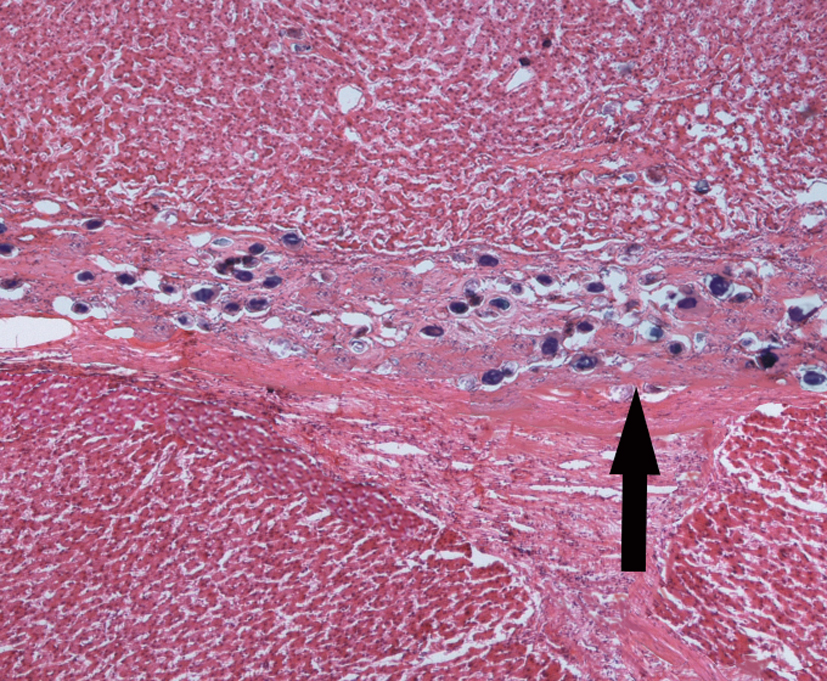

1.Epidemic cerebrospinal meningitis (purulent meningitis)

2.Encephalitis type B-liquefied necrosis

2.Encephalitis type B-2